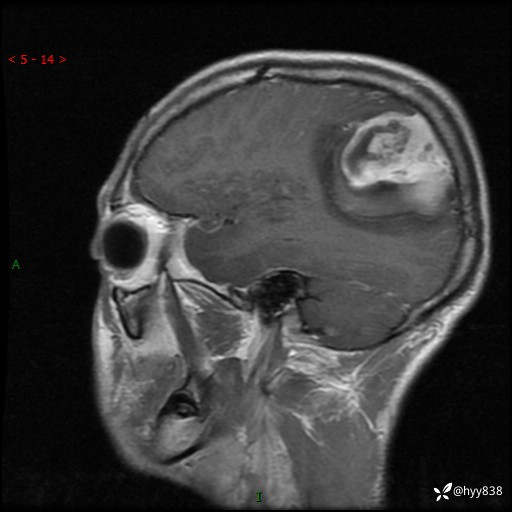

性别:男

年龄:21岁

简要病史:头痛伴呕吐半年,渐进性加重1月

颅脑MRI平扫+增强